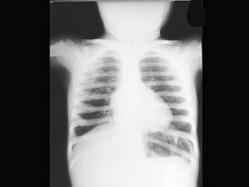

问题 男孩,4岁。自1岁起发现口唇青紫,活动后加剧,喜坐少动,心前区有ⅠⅡ级收缩期杂音,无震颤。胸片如图,下列哪一项与预后无关 ( )

选项 A、合并急性感染性心内膜炎 B、心电图示电轴右偏,左心室肥大 C、右向左分流量严重度 D、合并脑血栓 E、肺动脉狭窄严重程度

答案 B